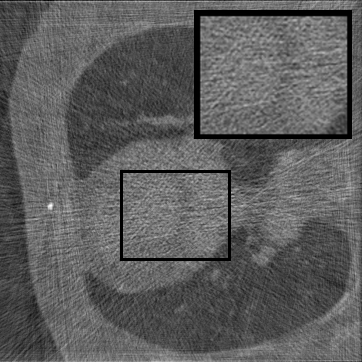

Figure 2: Qualitative inpainting results on TomoBank (lines 1 to 2) and LoDoPaB (lines 3 to 4) with random mask (ratio = 0.8) at 1024×\times1024 resolution. Odd columns and even columns show the sinograms and reconstructed images, respectively.

Inpainting Quality. Tab 2 summarizes accuracy results. At 2048×\times2048 resolution, HiSin achieves the best performance among all baselines while remaining memory-efficient, demonstrating its ability to extend high-quality inpainting to resolutions where other diffusion models fail. At 1024×\times1024, HiSin delivers accuracy comparable to its computation-intensive counterpart RePaint, showing that our optimizations do not compromise fidelity at moderate scales. Compared to DiffIR and HiDiffusion, HiSin consistently achieves higher SSIM and PSNR across mask ratios, with improvements up to +0.03 SSIM and +1.8 dB PSNR. Fig 2 visualizes sinogram inpainting and reconstructed images, where HiSin produces nearly indistinguishable results from RePaint. These findings confirm that HiSin fundamentally extends diffusion-based inpainting to 2048×\times2048 resolution in a more memory- and runtime-efficient manner.